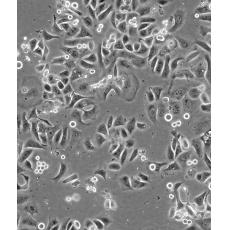

生長特性 adherent

形態特征 epithelial